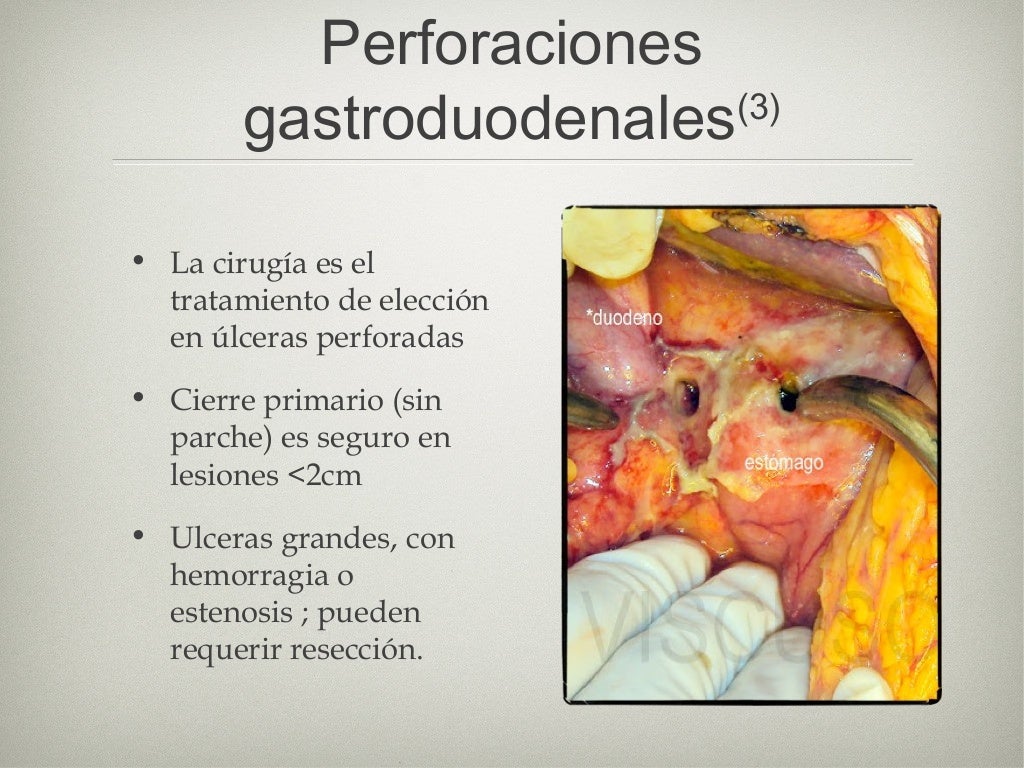

Sepsis abdominal fisiopatología, diagnóstico y tratamiento Medcmc